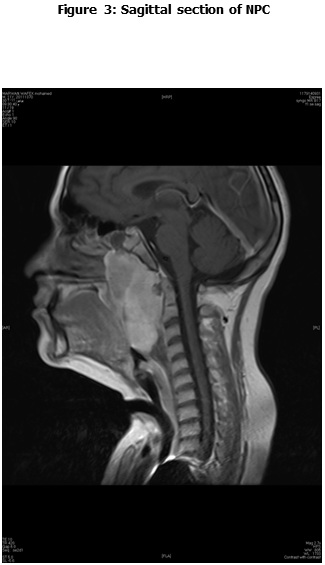

This is a retrospective study including all the newly diagnosed pediatric NPC who were diagnosed and treated at the Children Cancer Hospital Egypt (CCHE) during the period from July 2007 to December 2012. All imaging studies (e.g., CT or MRI scans) were reviewed by a senior head and neck radiologist for proper staging and assessment of tumor response. Patients were staged according to AJCC staging system. Modified version of the Response Evaluation Criteria in Solid Tumor (RECIST) was used to assess response.

This is a retrospective study including all newly diagnosed pediatric NPC at Children Cancer Hospital Egypt CCHE during the time period from July 2007 to December 2012. The patients' profiles were systematically reviewed for characteristics including pathology, laboratory, radiological work up and documented toxicities. All imaging studies (e.g., CT and MRI scans) were reviewed by a senior head and neck radiologist for proper staging and assessment of tumor response.

Pretreatment evaluation included a complete history and physical examination, complete blood count, serum biochemistry tests (including evaluation of electrolyte levels, hepatic and renal function tests), CT or MRI scans of the head and neck region, chest and bone scan. During therapy weekly examinations and laboratory evaluations were performed. Tumor response was assessed by clinical examination with appropriate MRI imaging studies after completion of neoadjuvant chemotherapy and at the end of radiotherapy.

The most common presentation was dysphagia seen in 23 patients (88.5%), followed by cervical lymphadenopathy in 21 (80.8%), and symptoms of increased intracranial pressure in 19 (73%) patients. The T1, T2, T3 and T4 tumor size was presented in 2 (7.7%), 5 (19.2%), 8 (30.8%) and 11 (42.3%) patients respectively. N0, N1, N2 and N3 was detected in 1 (2.8%), 8 (30.8%), 16 (61.5%) and 1 (3.8%) patients respectively. Three patients (11.5%) were metastatic at presentation.